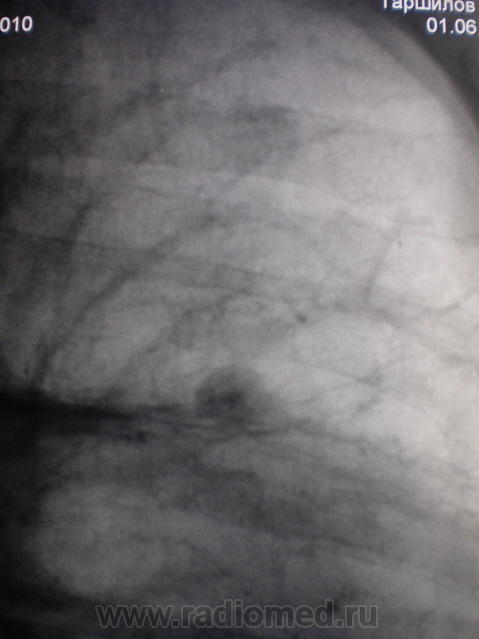

метастазы в легкие и плевру

был задан об одной "круглой тени" в S3. Решил, что гамартохондрома. Присмотревшись к окружающему фону и плевральным изменениям слева, не исключаю туберкулёму.

действительно круглая тень имеет плотный кальцинированный центр,что практически не характерно для злокачественных изменений за исключением метастазов из первичых опухолей кости (они в 90% случаев имеют кальцинаты на периферии ,а не в центре!!!).а так 3 диагноза:1)туберкулема,2)гамартома,3)гистоплазмоз.на счет участков выше ,если присмотреться повнимательнее ,то участок представляет собой сгруппировавшиеся мелкие (ацинарные) очаги по типу дерева в почках,отражающий эндобронхиальный рост,выпот слева-так что в первую очередь надо исключить туберкулез

Я, конечно, сильно извиняюсь, но кажется и правом лёгком не меньше округлых теней. Да и реакция плевры, полюс левосторонний гидроторакс. Искать, искать и ещё раз искать (всегда думал В.И.Ленин)

Я спрашивал про ту, что желтой стрелкой помечена, первично утаив ту, что потом пометил красной стрелкой.